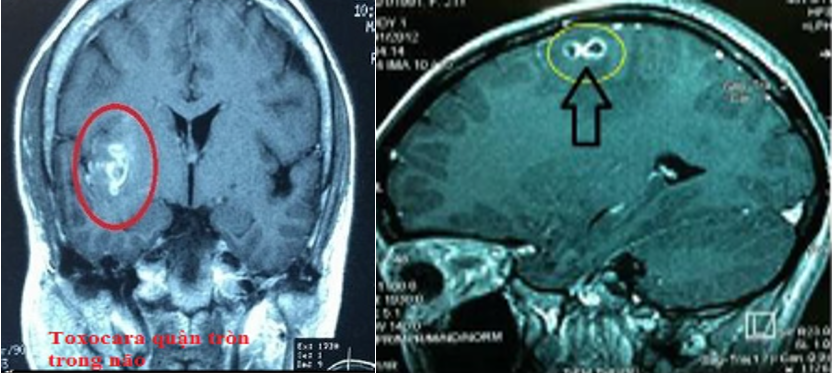

4.4 Thể ấu trùng di chuyển hệ thần kinh: Đây là thể bệnh nguy hiểm so với các thể khác. Các triệu chứng không đặc hiệu, mức độ biểu hiện phụ thuộc vào vị trí tổn thương ở hệ thần kinh như: Sốt, đau đầu, co giật.

5.2 Chẩn đoán hình ảnh

- Chụp cắt lớp vi tính: Có hình ảnh thay đổi tỷ trọng tương ứng với vùng tổn thương

- Chụp MRI các cơ quan nghi tổn thương: phát hiện thay đổi tín hiệu tương ứng các vùng tổn thương.